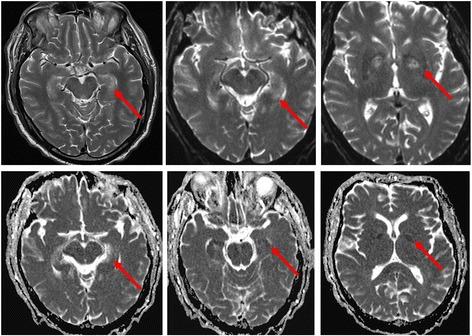

Hypoxic ischemic brain injury (HIBI) after cardiac arrest (CA) is a leading cause of mortality and long-term neurologic disability in survivors. The pathophysiology of HIBI encompasses a heterogeneous cascade that culminates in secondary brain injury and neuronal cell death. This begins with primary injury to the brain caused by the immediate cessation of cerebral blood flow following CA. Thereafter, the secondary injury of HIBI takes place in the hours and days following the initial CA and reperfusion. Among factors that may be implicated in this secondary injury include reperfusion injury, microcirculatory dysfunction, impaired cerebral autoregulation, hypoxemia, hyperoxia, hyperthermia, fluctuations in arterial carbon dioxide, and concomitant anemia.Clarifying the underlying pathophysiology of HIBI is imperative and has been the focus of considerable research to identify therapeutic targets. Most notably, targeted temperature management has been studied rigorously in preventing secondary injury after HIBI and is associated with improved outcome compared with hyperthermia. Recent advances point to important roles of anemia, carbon dioxide perturbations, hypoxemia, hyperoxia, and cerebral edema as contributing to secondary injury after HIBI and adverse outcomes. Furthermore, breakthroughs in the individualization of perfusion targets for patients with HIBI using cerebral autoregulation monitoring represent an attractive area of future work with therapeutic implications.We provide an in-depth review of the pathophysiology of HIBI to critically evaluate current approaches for the early treatment of HIBI secondary to CA. Potential therapeutic targets and future research directions are summarized.

心脏骤停(CA)后的缺氧缺血性脑损伤(HIBI)是幸存者死亡和长期神经功能残疾的主要原因。HIBI的病理生理学包括一个异质性级联反应,最终导致继发性脑损伤和神经元细胞死亡。这始于CA后脑血流立即停止所导致的原发性脑损伤。此后,HIBI的继发性损伤发生在初始CA和再灌注后的数小时和数天内。可能与这种继发性损伤有关的因素包括再灌注损伤、微循环功能障碍、脑自动调节受损、低氧血症、高氧血症、高热、动脉二氧化碳波动以及合并贫血。阐明HIBI的潜在病理生理学至关重要,并且一直是确定治疗靶点的大量研究的重点。最值得注意的是,靶向温度管理已被严格研究用于预防HIBI后的继发性损伤,与高热相比,其与改善预后相关。最近的进展表明,贫血、二氧化碳紊乱、低氧血症、高氧血症和脑水肿在HIBI后的继发性损伤和不良后果中起重要作用。此外,使用脑自动调节监测对HIBI患者进行灌注靶点个体化的突破代表了一个具有治疗意义的未来有吸引力的工作领域。我们对HIBI的病理生理学进行了深入综述,以批判性地评估目前对CA继发的HIBI进行早期治疗的方法。总结了潜在的治疗靶点和未来的研究方向。